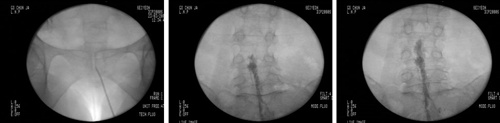

최근에는 이처럼 수술적 치료가 필요하지는 않으나 증상이 있는 환자에게서 감압신경성형술이 큰 호응을 얻고 있다. 감압신경성형술은 가느다랗고 긴 특수의료기기 카테타를 이용하여 척추관과 연결되어 있는 꼬리뼈의 작은 구멍들을 통해 척추 신경 부위로 접근하는 방식이다.

RACZ는 카테터를 척추 신경 부위로 접근시킨 후 특수 약물을 주입해주는 방법이다. 전신 마취 없이 시행하므로 환자들의 부담이 상대적으로 덜하며 30-40분 내의 시간이 소요된다. 치료는 비교적 간단히 진행되지만 환부의 정확한 위치에 카테터를 삽입하는 것이 중요하므로 시술은 경험이 많은 전문의에게 의뢰하는 것이 좋다.

과정은 요추 신경공으로 들어가거나 꼬리뼈 쪽으로 도관을 설치한 후 도관을 통하여 기구(카테터)를 넣어 치료 목표 위치로까지 기구를 도달시킨 다음에 주사를 주입하게 된다. 약물이 병변에 작용하면 염증을 가라앉히고 부종을 감소시켜주어 증상을 완화시킨다.

<사진>약물이 병변에 도달하는 모습(아래). /연세사랑병원 제공.